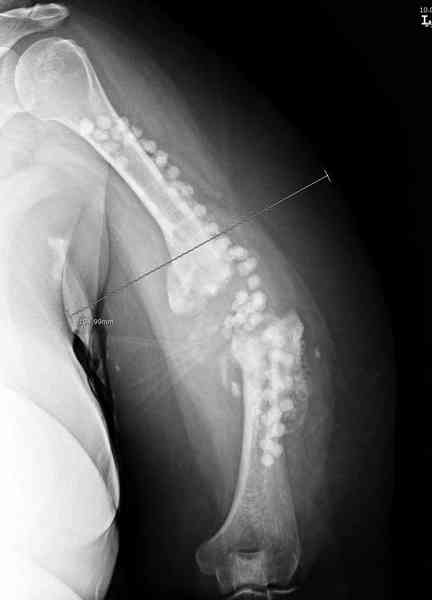

Хотя сам не стороннник применения более массивных

имплантов для плеча, но для этого случая сделали

исключение. На снимке 4А диаметр мягких ткани около 20 см, при весе больной более 135 кг, и также выступление Андрея Волны подстегнуло к применению более массивной 4.5 мм локинг пластины.

А для стимулирования мы применили массу из состава:

OP1 с деминерализованной костью, добавив к ним еще

красную часть, приготовленную из крови больной.

Взятая перед операцией кровь в количестве 80 мл

провели через центрифугу и без сывороточной части

красную матрицу добавили к остальным.

С такой массой наверное ложный сустав "over killed", но надеюсь, что-то из них при такой фиксации окажет стимулирующее действие.